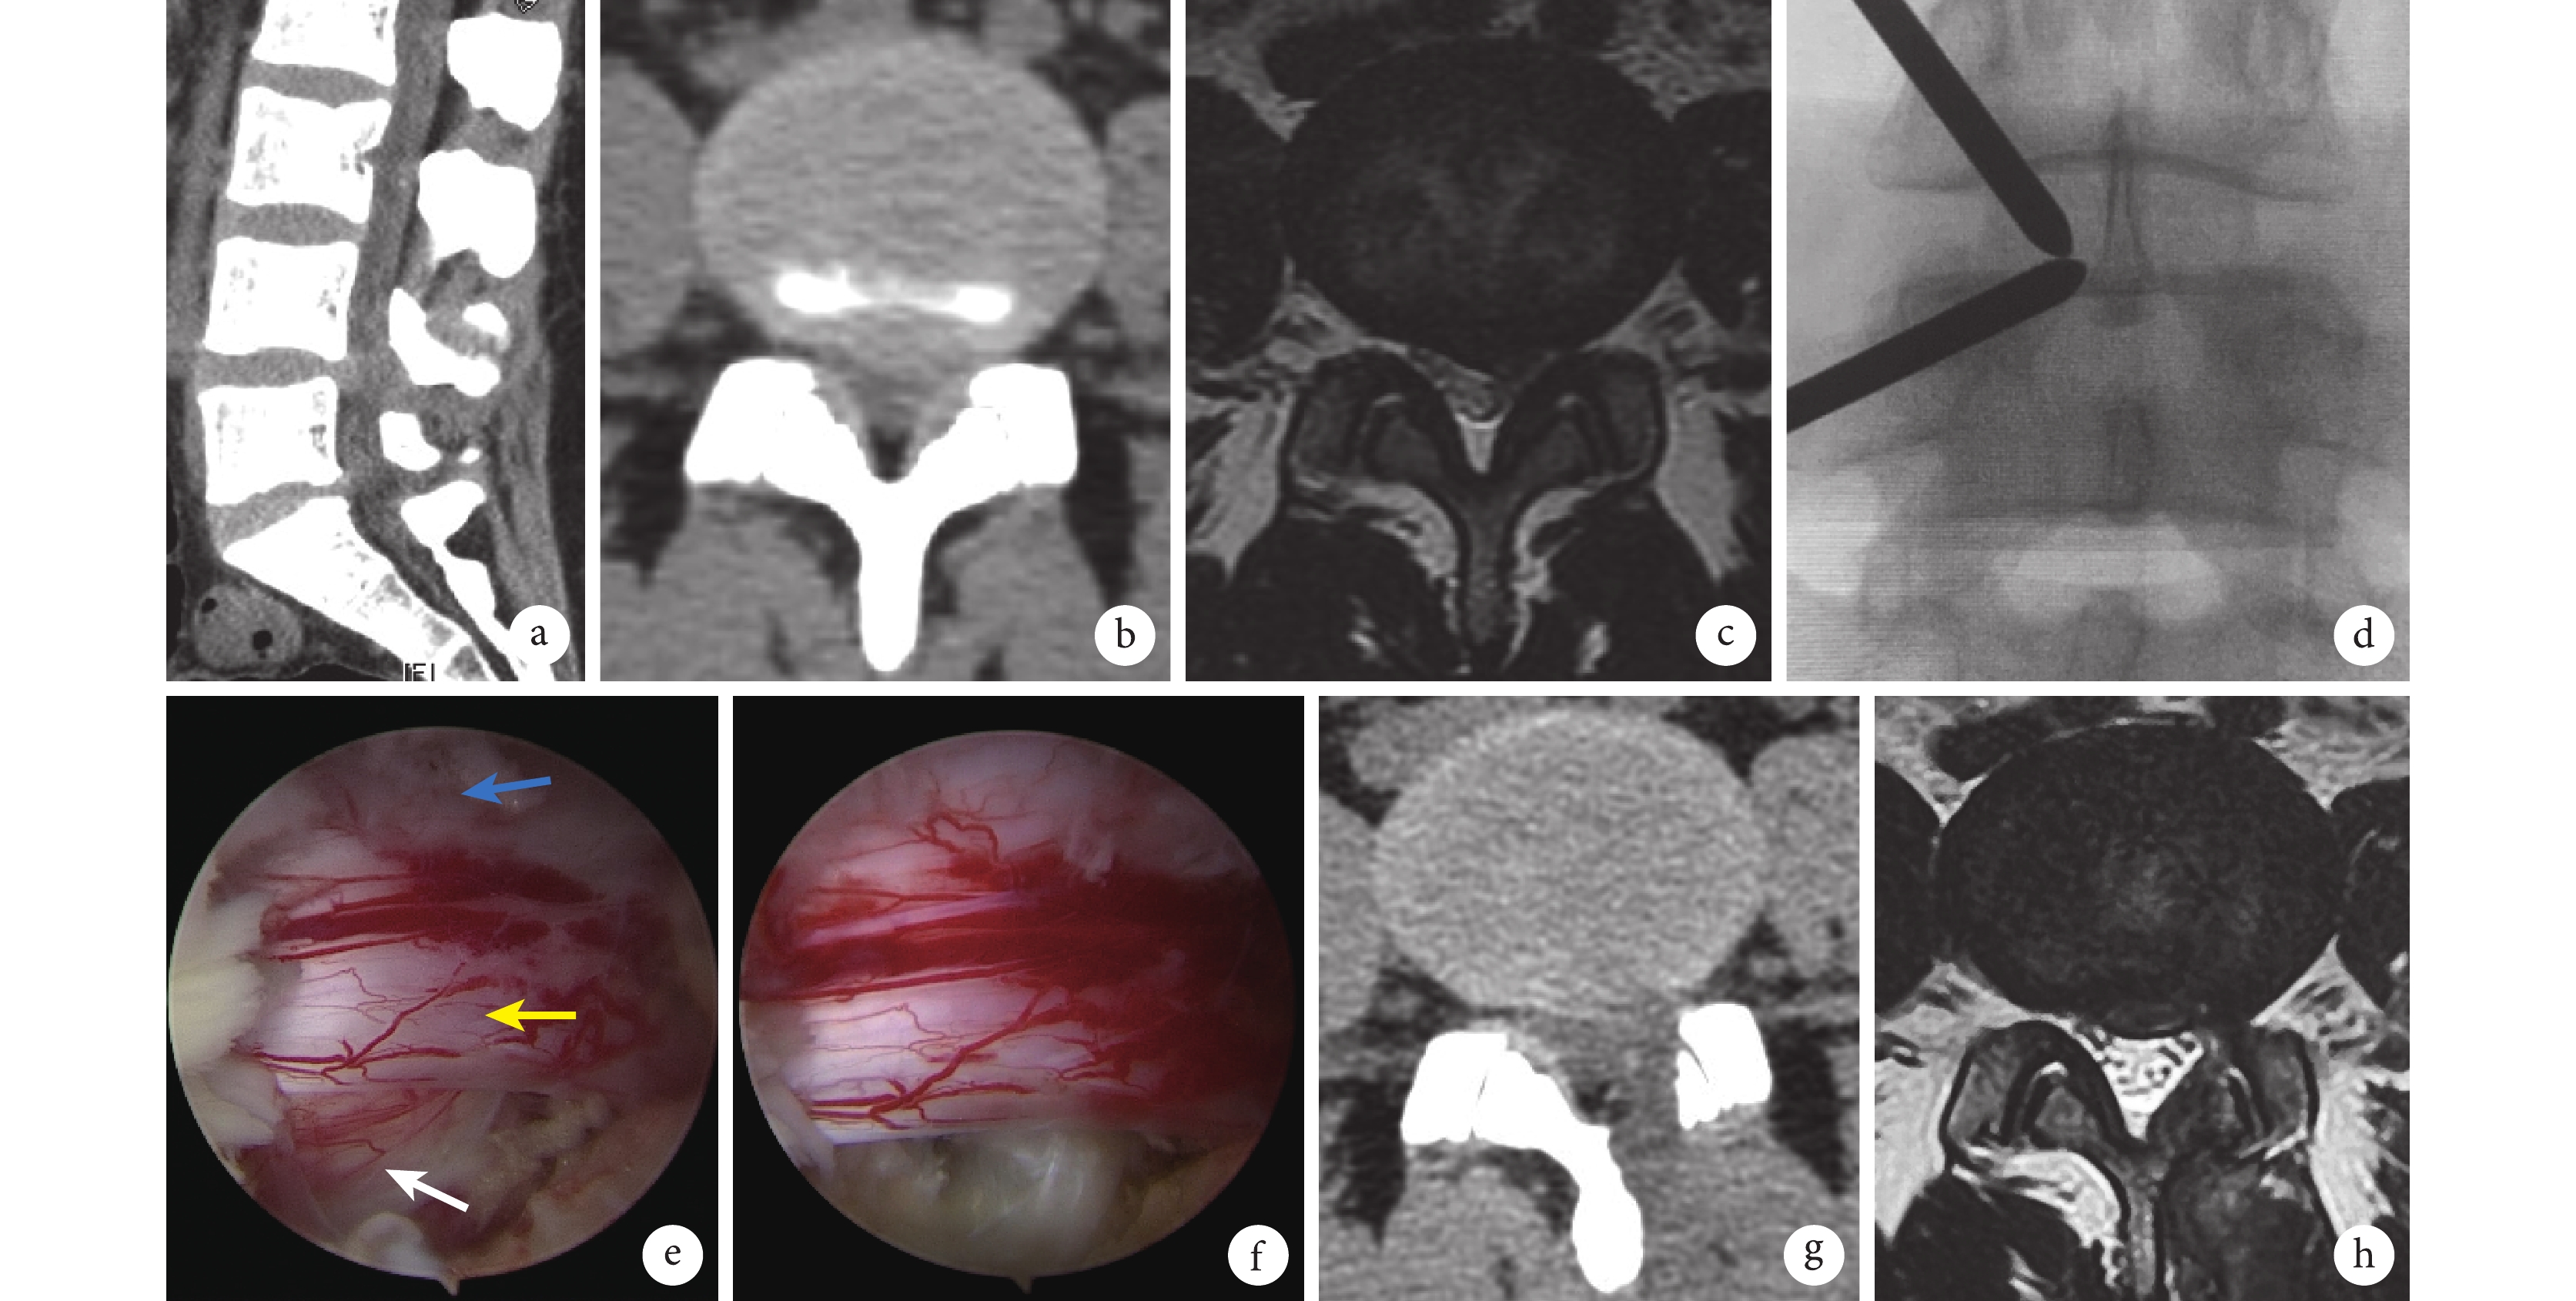

a. 術前CT矢狀位示L4、5椎間盤突出;b. 術前CT橫斷位示L4、5中央區及左旁正中區椎間盤突出;c. 術前MRI橫斷面示L4、5椎間盤中央偏左突出,并擠壓左側L5神經根及硬膜囊;d. 術中將導向器交集于L4椎板下緣;e. 術中內鏡下左側L5神經根受壓狀態(白箭頭示突出椎間盤,黃箭頭示左側L5神經根,藍箭頭示硬膜囊);f. 術中內鏡下見突出髓核摘除后神經根松弛,表面血運恢復;g. 術后1 d CT橫斷位示L4、5大部分關節突保留;h. 術后6個月MRI橫斷面示硬膜囊形態基本恢復,雙側L5神經根無受壓

Figure2. A 33-year-old female patient with LDH at L4, 5 on left sidea. Preoperative CT sagittal view showed L4, 5 disc herniation; b. Preoperative CT transverse view showed L4, 5 disc herniation in the central region and the left para-central region; c. Preoperative MRI transverse section showed L4, 5 disc herniation to the left of center with compression of left L5 nerve root and dural sac; d. Intraoperative intersection of the guide at the lower edge of L4 lamina; e. Microscopically, the compression state of the left L5 nerve root was displayed (white arrow showed the herniated disc, yellow arrow showed the left L5 nerve root, blue arrow showed the dural sac); f. Microscopically, nerve root relaxation and surface blood supply recovery were observed after excision of protruding nucleus pulposus; g. CT transverse view at 1 day after operation showed most of the L4, 5 articular processes retained; h. MRI transverse section at 6 months after operation showed that the shape of the dural sac was basically restored, and there was no compression of bilateral L5 nerve roots